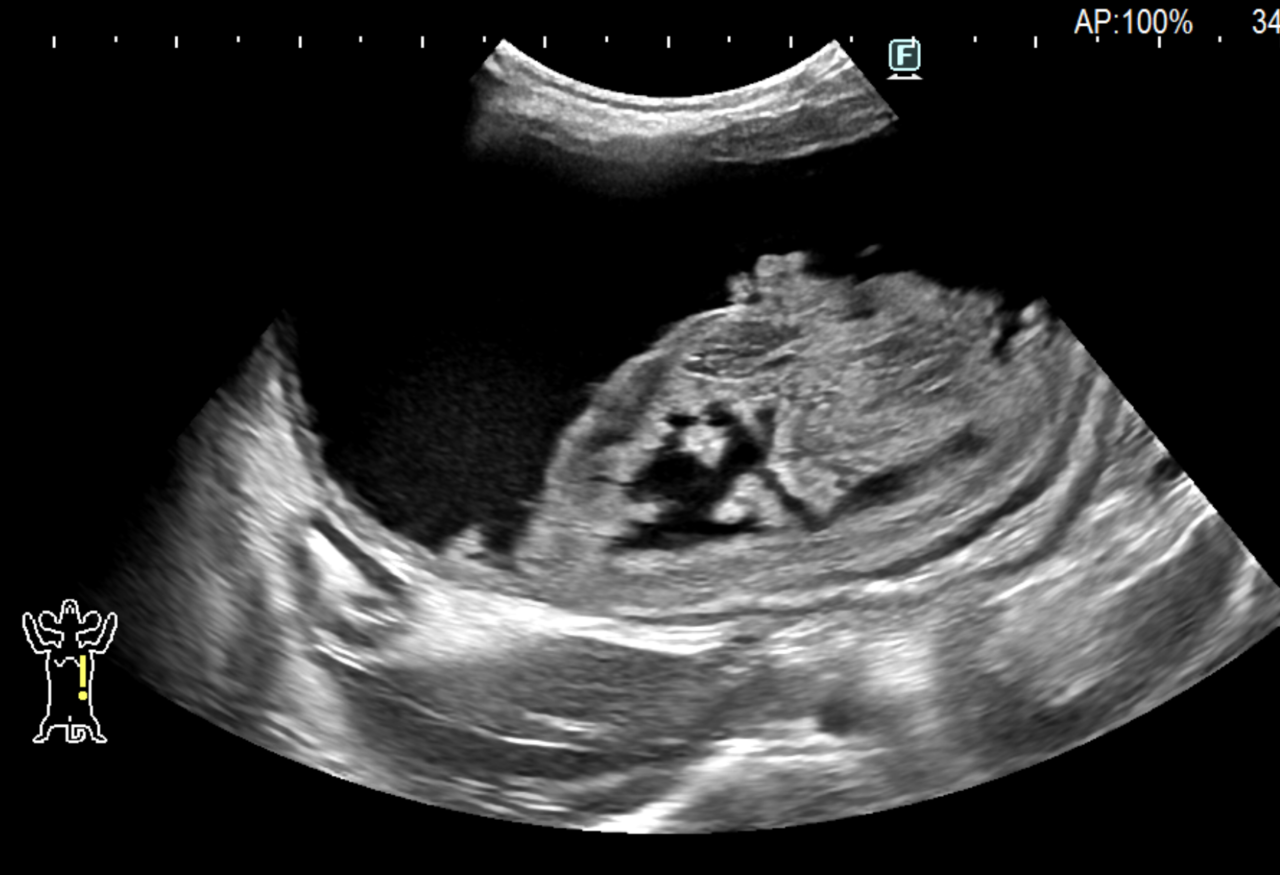

画像診断:特徴的な所見は述べらていませんが、CTで子宮の捻転基部が観察されました。